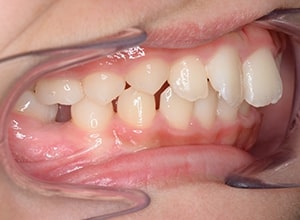

| 主訴 | 右下6近心傾斜、上顎前歯のでこぼこ | 診断名 | 下顎右側第一大臼歯近心傾斜、 上顎左側第一大臼歯近心傾斜症例 |

| 初診時年齢 | 11歳6ヵ月 | 性別 | 女 | 動的治療期間 | 5ヵ月 | ||

| 口腔内所見 | over jet 3.5mm,over bite4.0mm、下顎正中右側偏位2.0mm、大臼歯関係は左側Ⅰ級であったが、右下6は右下E早期喪失のため近心傾斜しておりⅢ級の臼歯関係となっていた。また上下顎前歯は軽度の叢生を呈していた。 |